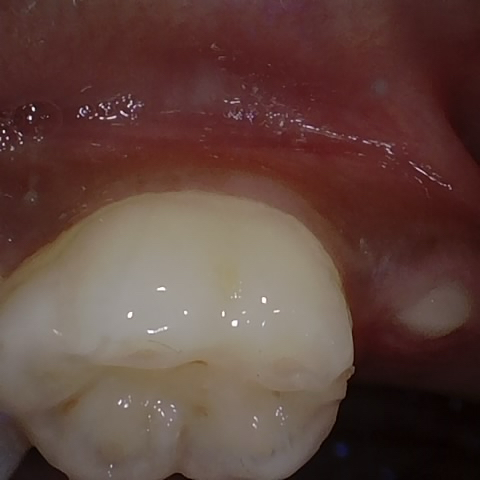

Annotated as "Good"